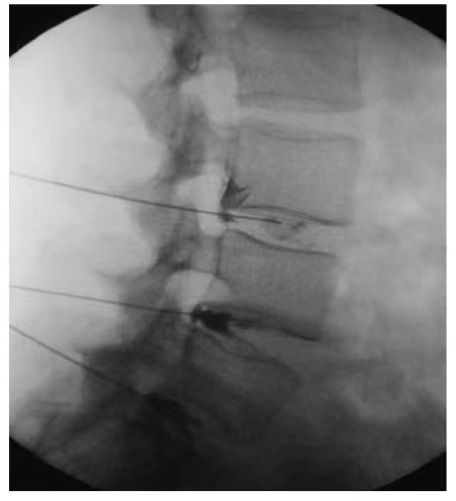

CT引导的脊柱注射:精确愈合,新希望

我们的专家团队开创了CT引导的主要注射技术,专为脊髓损伤治疗中的干细胞疗法而设计。在过程中,实时CT成像会生成脊柱的动态3D视觉效果,从而使外科医生可以旋转和分析多维空间中的断裂位置。通过健康的解剖途径,小心地将针头前进,避免了骨障碍物。当外科医生将针引导针对脊髓时,系统会连续更新成像,以验证脊髓和椎骨之间的轨迹角度和空间关系,以确保绝对的精度和安全性。该技术通常与腰椎穿刺或静脉内干细胞疗法结合使用,以增强功效。

CT引导的脊柱注射的优势:

1.微创和安全

不需要重大切口。在局部麻醉下进行,以最小的创伤,失血和后术后疼痛进行,从而可以快速康复。

2。亚毫米精度

CT引导允许以无与伦比的精度实时测量和靶向伤害部位。

CT引导的脊柱注射为脊髓损伤患者提供了开创性,安全且有效的解决方案,可显着改善临床结果和生活质量。如果您或亲人正在与脊髓损伤作斗争,请立即咨询我们的专业医疗团队。我们将共同制定一个个性化的治疗计划,以重新点燃希望并赋予您重新独立的旅程。